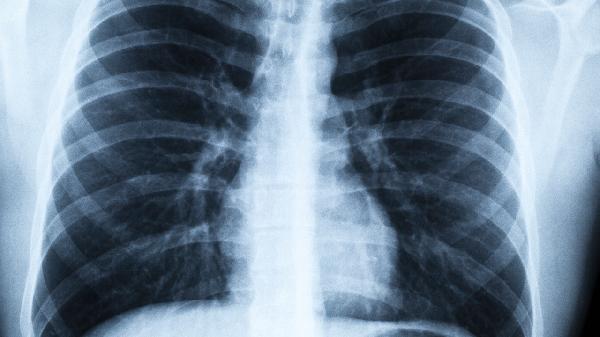

病毒性肺炎的临床表现有哪些

病毒性肺炎的临床表现主要有发热、咳嗽、气促、胸痛、乏力等。病毒性肺炎通常由流感病毒、呼吸道合胞病毒、腺病毒等病原体感染引起,不同病毒导致的症状严重程度存在差异。